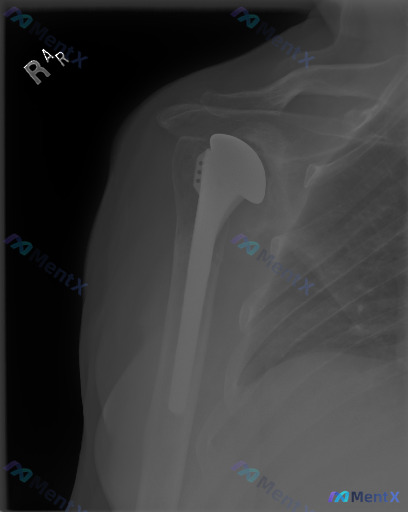

右肩关节置换术后X光片,第一眼觉得稳定,但有没有被漏掉的异常?

整理到一份右肩关节置换术后的正位X光片资料,第一眼读下来感觉很稳:

- 肱骨假体位置居中,骨-假体界面没看到明显的透亮线

- 肱骨头和关节盂对位也正常,没有脱位

- 周围骨质密度还行,没看到明确骨折或破坏

- 软组织也没肿,没看到明显钙化

但资料里特别提到了几个点:金属伪影会不会挡住了什么?早期松动会不会在X光上是“静默”的?